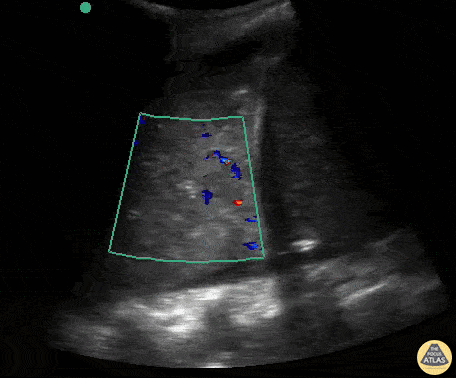

Pulmonary - Color Doppler of Consolidation in Pneumonia

Massive lobar consolidation showing pulsatile flow on color doppler, befitting pneumonia. Contributor: Rafael Intensivanaveia